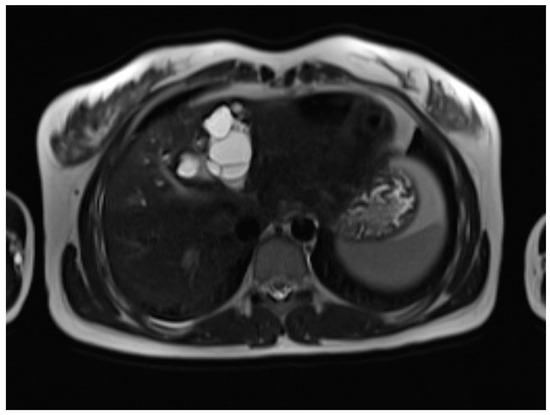

A liver MRI scan confirmed a cystic structure with multiple daughter cysts, hypointense on a T1-weighted image (T1WI), and hyperintense on a T2-weighted image (T2WI), with no solid components, no signs of membrane rupture, and a maximum diameter of 10 cm (craniocaudal) (Figure 1). Additionally, elevated signals on T2WI in the surrounding liver tissue were found. The T1 sequences did not reveal any contrast uptake after 5 (Figure 2), 10, or 20 (Figure 3) minutes post-injection. Furthermore, DWI/ADC mapping indicated a hydatid cyst. The DWI sequences included a trace DWI (Figure 4), an ADC map (Figure 5), and both at b800. Radiomics and AI tools were not involved. The trace DWI showed an area of hypointensity in the region of the cyst that was surrounded by a hypointense layer, depicting the cystic wall. The ADC map revealed hyperintensity within the area, in concordance with a typical depiction of cysts on an MRI scan.

First MRI scan: Axial T1W MRI scan showing hypointense daughter cysts in liver segment IV with no contrast uptake after 5 min.

Second MRI scan: Axial T1W native MRI scan, where the floating membranes are rather difficult to depict, with the hypointense area in liver segment IV showing the cyst.